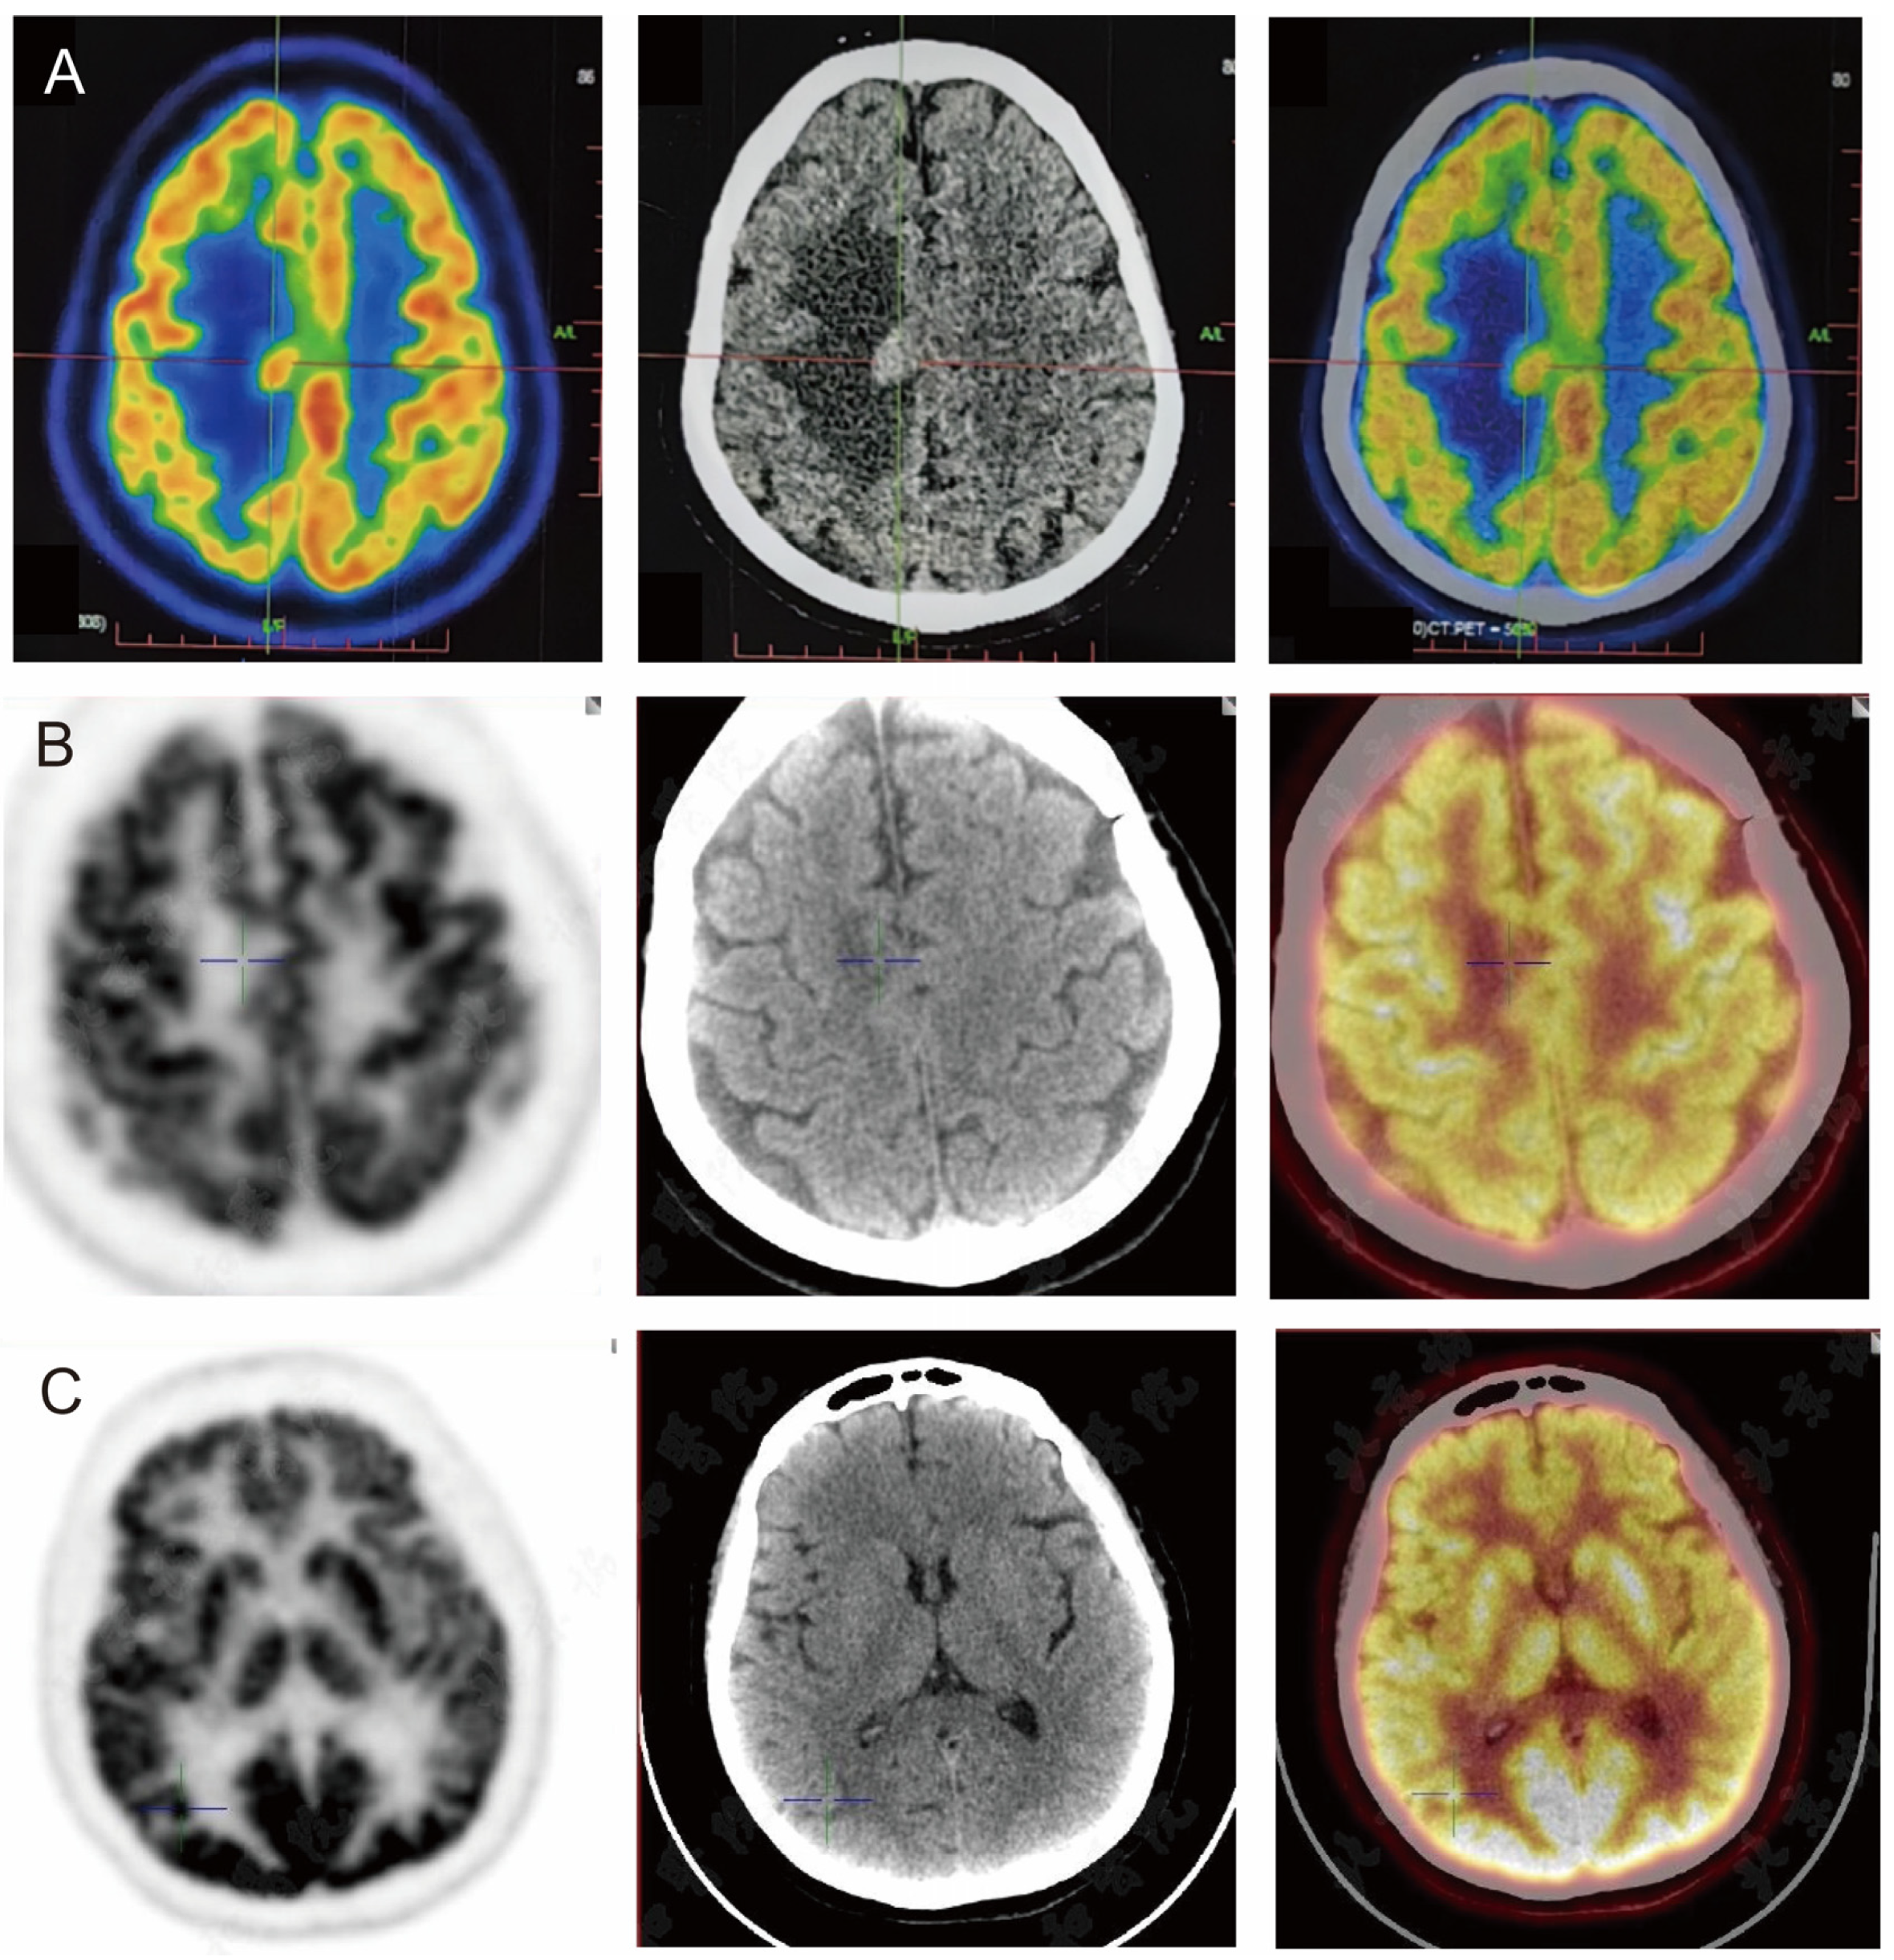

| PET/CT (4.22): hypermetabolic foci with peripheral odema in the right centrum semiovale; uneven metabolism in left lobe glands, multiple slightly hypermetabolic lymph nodes in neck and mediastinum bilaterally | |

| PET/CT (7.8): A metabolically increased nodule in the right occipital lobe (SUVmax 17.4); a nodule in the right centrum semiovale and the right subject lobe, with metabolism lower than that of the cortex | |